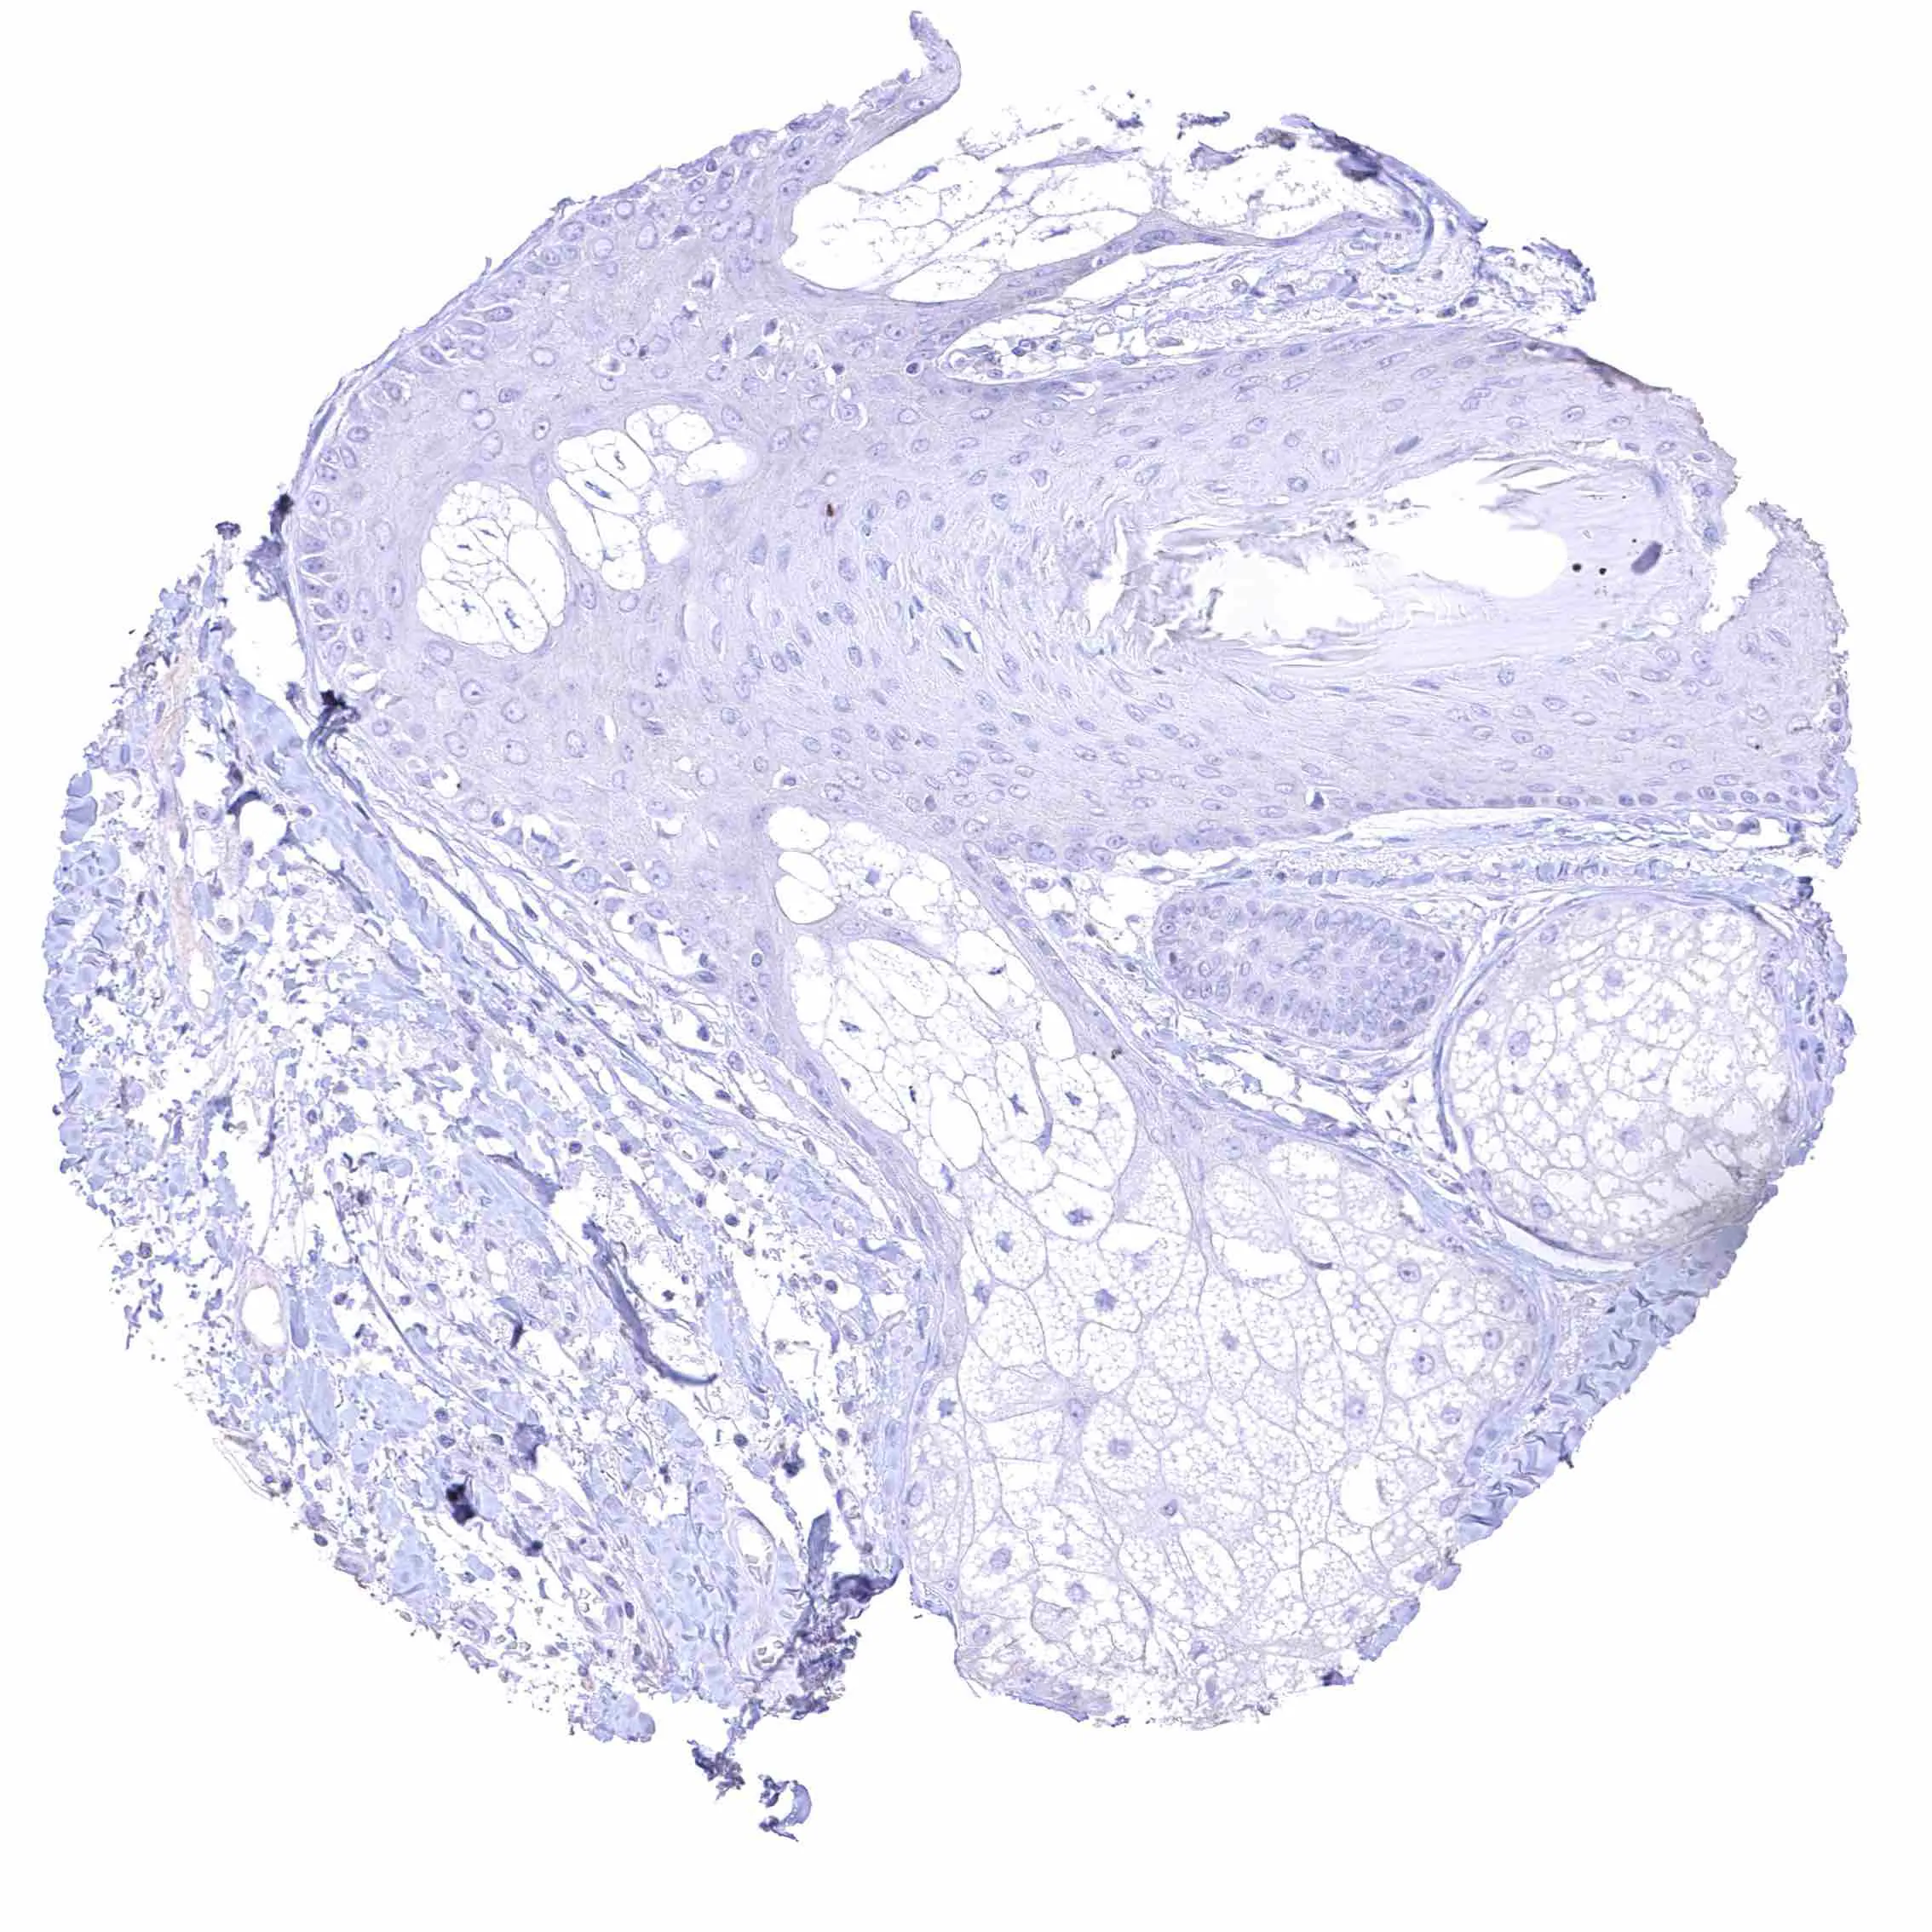

Uterus, ectocervix